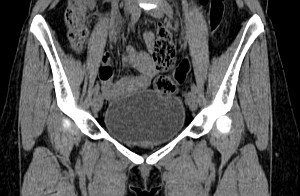

Мужской малый таз

Женский малый таз

Тазобедренные суставы